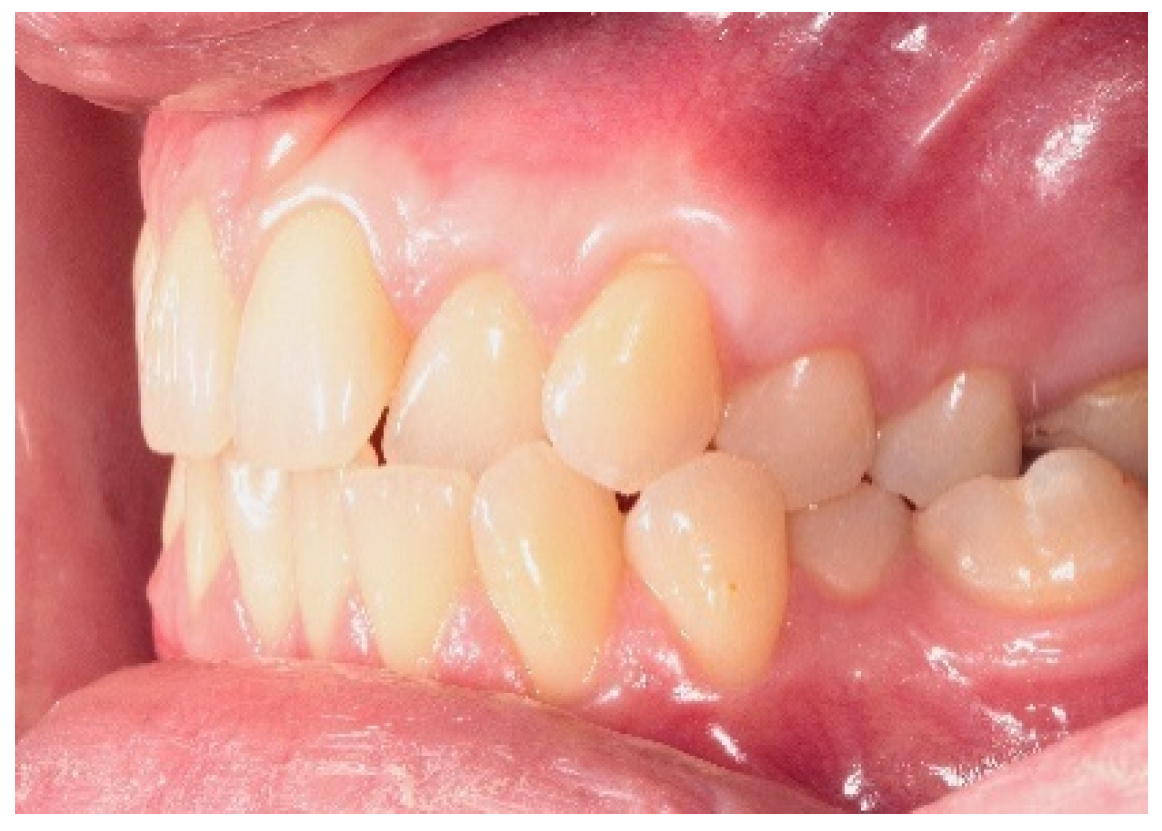

3.1. Clinical Measurements for CAL and GRD

3.2. Clinical Measurements for GRW, PD and AG

3.3. Clinical Measurements for BGT1, BGT2, BGT3

3.4. Clinical Values for %BGT1, CRC and ARC